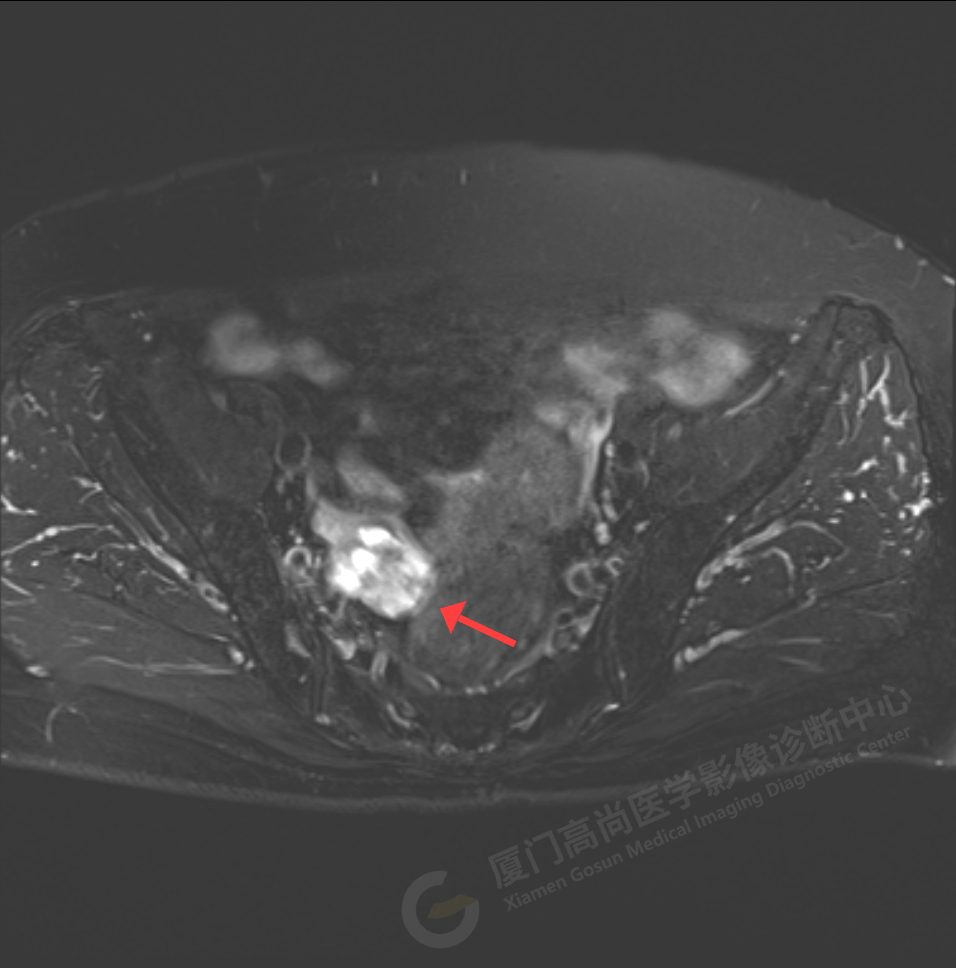

磁共振影像圖

我中心為陳阿姨安排了影像解讀及專家會診,經(jīng)過專家綜合分析,給出了初步診斷意見:右側(cè)附件區(qū)囊實性占位伴腫大淋巴結(jié),考慮卵巢來源惡性腫瘤,卵巢Ca可能性大。醫(yī)生建議盡快做進一步的檢查及就診。

陳阿姨家人經(jīng)過多方打聽和聯(lián)系,陳阿姨于5月18日至廣東中山大學附屬腫瘤醫(yī)院會診及手術,術后病理顯示:卵巢高級別漿液性癌2期,證實了高尚專家的判斷。